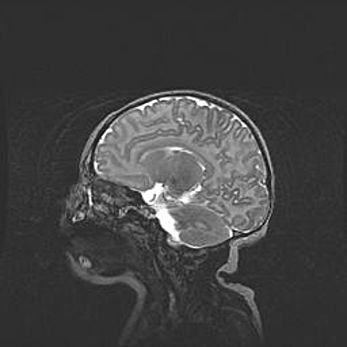

Открытая гидроцефалия.

Возраст: 9 месяцев 12 дней

Вес: 6800 г

Пол: мужской

Окружность головы: 41,5 см

Срок гестации: 28 недель

Гидроцефалия головного мозга у новорожденных имеет характерный признак: опережающий рост окружности головы приводит к визуально хорошо определяемой гидроцефальной форме сильно увеличенного в объёме черепа. Детские неврологи определяют следующие симптомы гидроцефалии у грудничков: выбухающий напряжённый родничок, частое запрокидывание головы, смещение глазных яблок к низу.